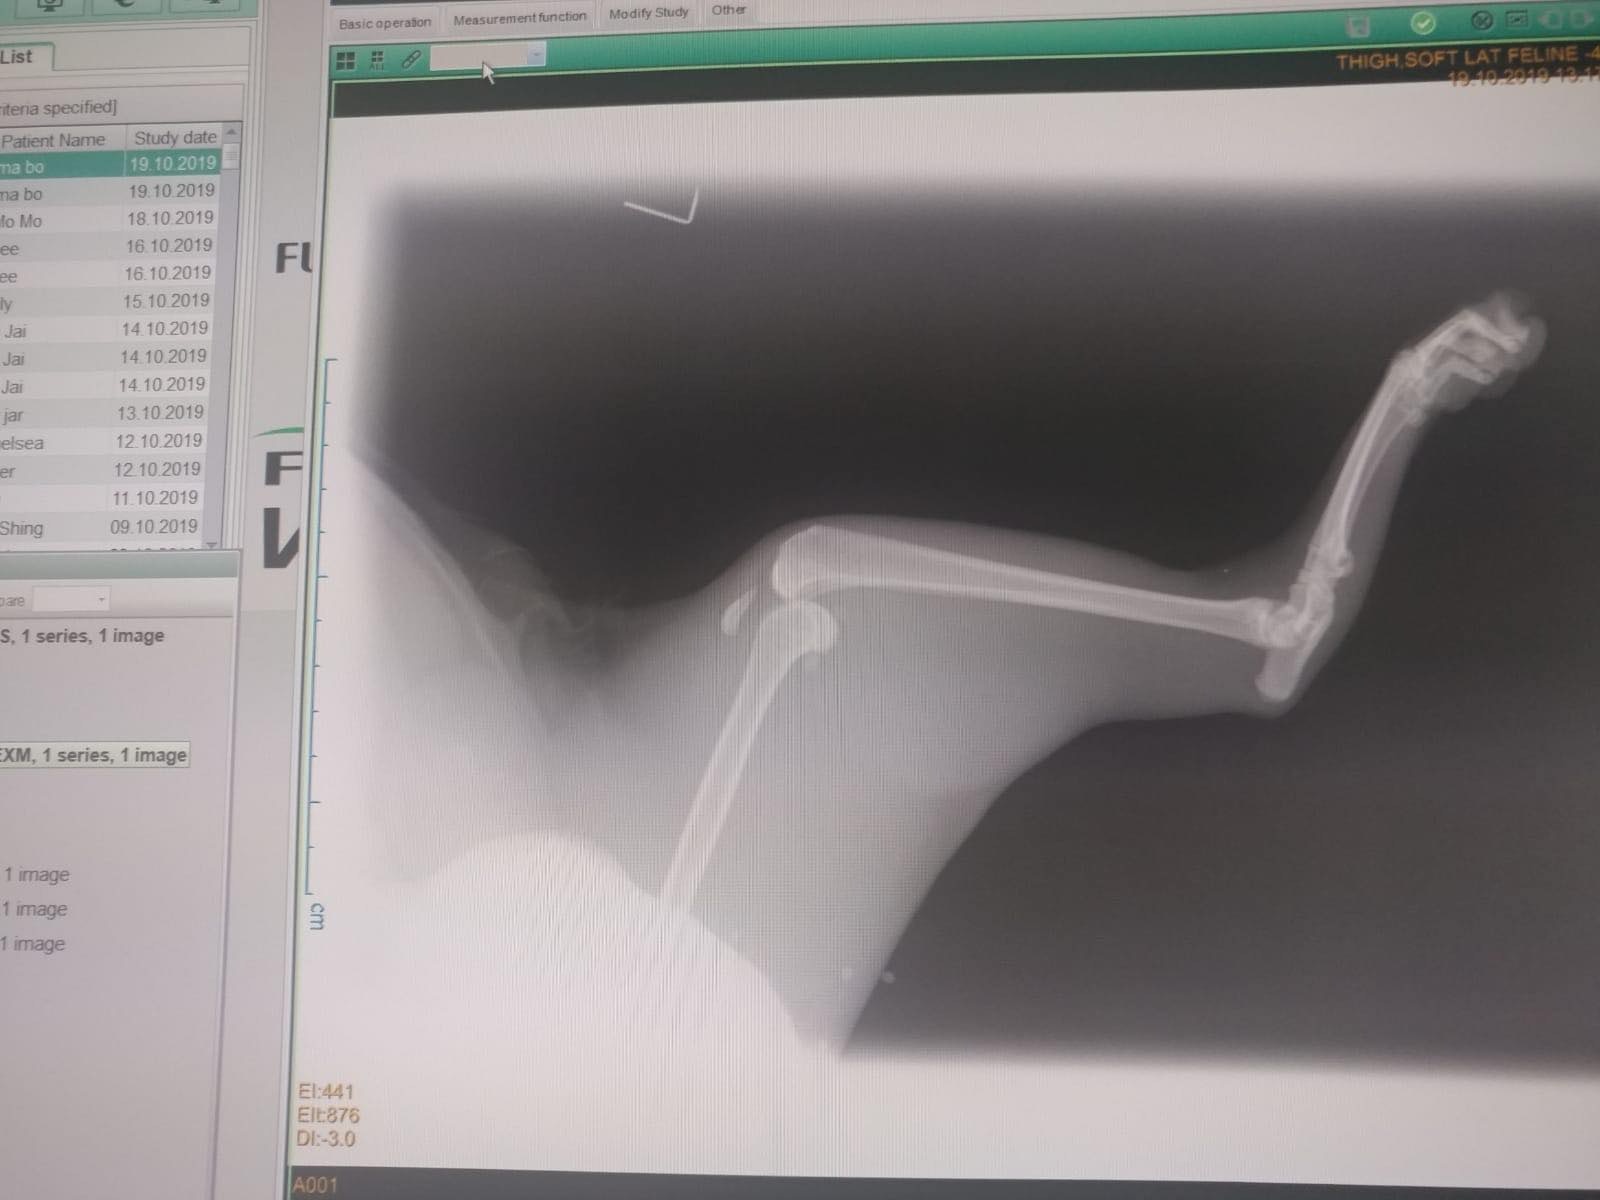

媽寶的下半身有多處嚴重受傷,膀胱有異樣,左腳骨折、膝蓋移位、韌帶斷裂,右腳盆骨脫骹。醫生先後兩次為牠做緊急手術,取出腹中的死胎,並治療膀胱、右腳,及後需要做第三次手術會再為牠的下肢做手術。